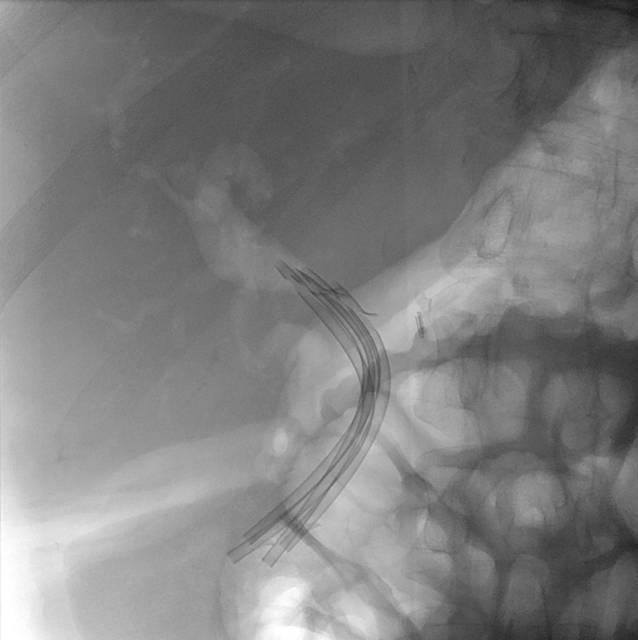

Zuletzt wurde im ESCAPE-Trial die Überlegenheit der chirurgischen Therapie bei Patienten mit kurzzeitiger Opioidtherapie und einem erweiterten Ductus pancreaticus über 5 mm gegenüber der endoskopischen Therapie im Sinn einer besseren Schmerzkontrolle nachgewiesen [22]. Damit ist die operative Sanierung für symptomatische Pankreasgangstenosen mit seit Kurzem bestehender Opioidpflichtigkeit indiziert. Da sie jedoch mit einer höheren Letalität vergesellschaftet ist, kann auch initial ein 3‑monatiges Stenting des Pankreasgangs erfolgen; bei fehlender Besserung (Evaluierung nach 6 bis 8 Wochen) ist die operative Sanierung erneut in Betracht zu ziehen [1, 15]. Die Operation zeigt sich auch bei rezidivierenden, symptomatischen Pankreasgangsteinen der endoskopischen Therapie überlegen [1]. Symptomatische Pseudozysten sollten primär endoskopisch und je nach Lokalisation und Größe transpapillär oder endosonographisch gezielt transmural abgeleitet werden. Bei Rezidiven kann eine chirurgische Sanierung erfolgen. Auch bei einer biliären Stenose steht die endoskopische Versorgung mittels 12-monatigem Stentingprogramm im Vordergrund (Abb. 3). Die chirurgische Sanierung ist nach Therapieversagen indiziert. Das Stenting erfolgt bei Gallengang- und Pankreasgangstenosen mit Plastikstents oder fcSEMS („fully covered self-expanding metal stents“; [1, 15]). Mittels neuer Generationen von biodegradablen Stents lässt sich die Anzahl der Interventionen bei einem Stentingprogramm von pankreatischen oder biliären Stenosen potenziell verringern (Abb. 4a, b). Langzeitdaten hinsichtlich des Nebenwirkungsprofils sowie der Kosten-Nutzen-Effizienz liegen allerdings noch nicht vor. Eingeblutete Pseudozysten sowie Pseudoaneurysmata sind primär einer angiographischen Intervention zuzuweisen [4].

Abb. 3

Vierfachstenting in einer Gallengangstenose im Rahmen einer chronischen Pankreatitis